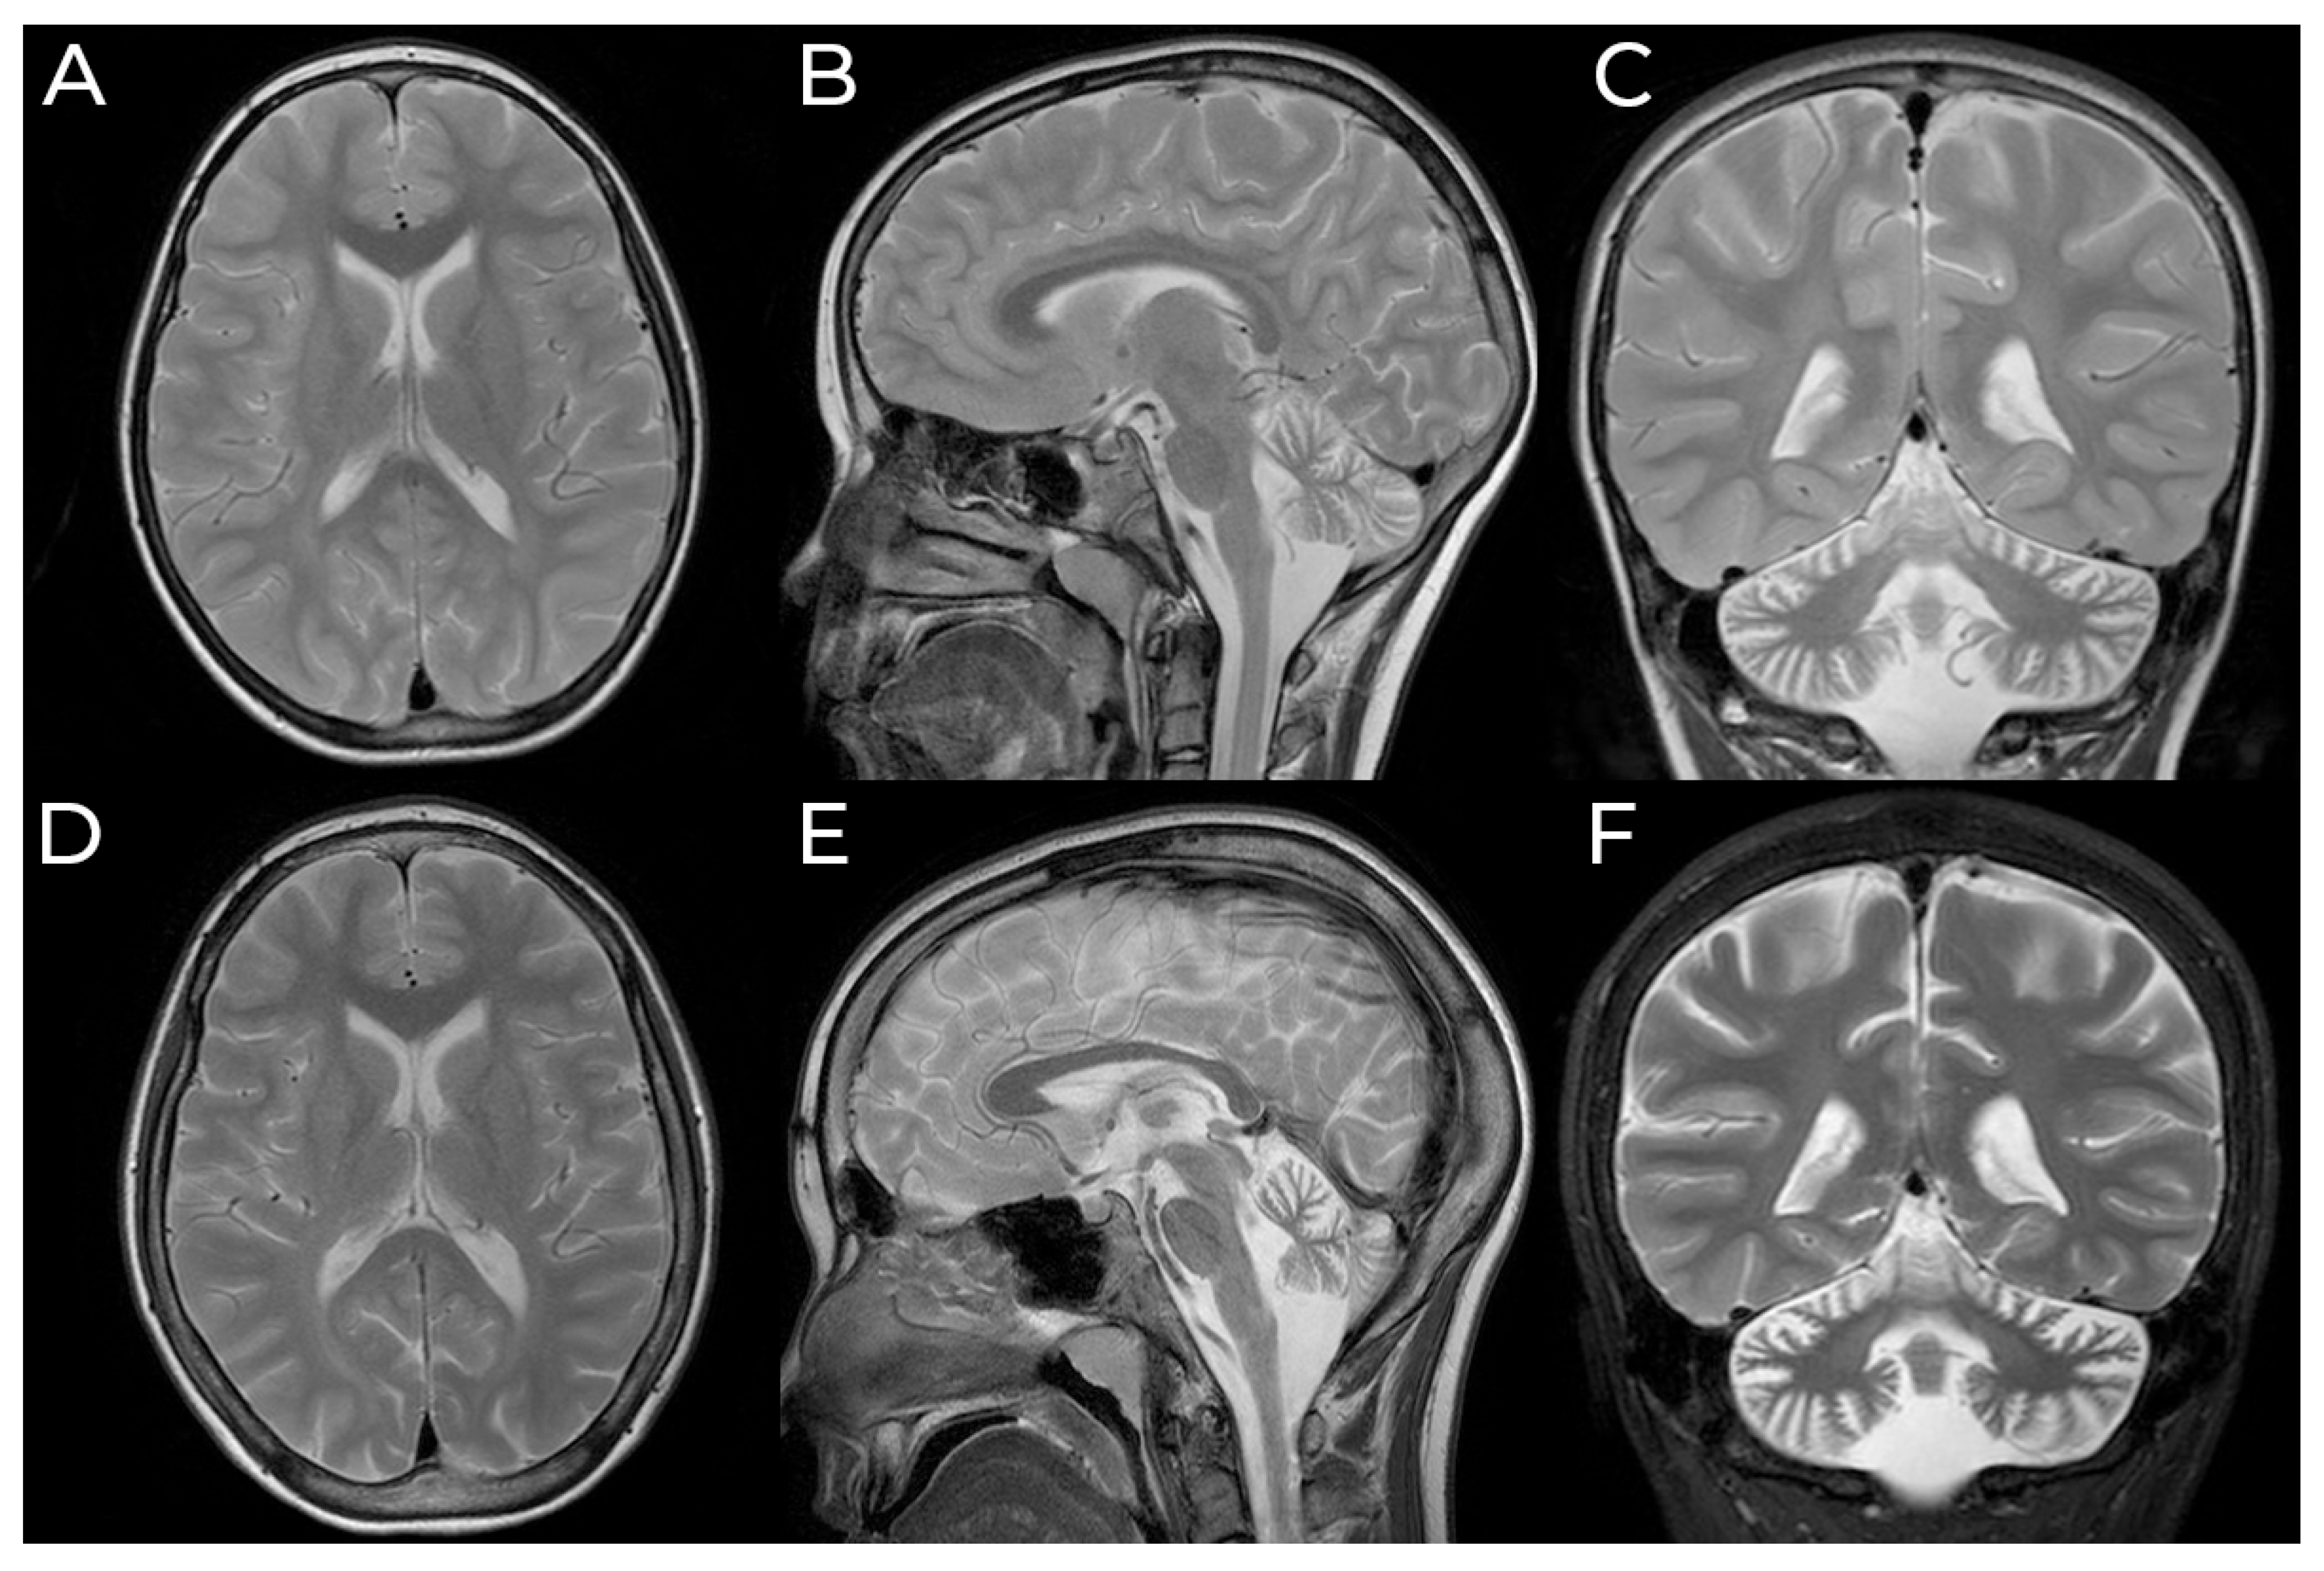

| Cerebral MRI | Atrophy at later stages | N/A | Atrophy | N/A | Atrophy | Cortical atrophy | Atrophy, T2/FLAIR PV WM hyperintensivities | Atrophy, T2/FLAIR WM hyperintensivities |

| Cerebellar atrophy | Yes | N/A | Yes | N/A | Yes | Yes | Yes | Yes |

| Cerebral MRI | Diffuse atrophy (1/3), Mild atrophy (1/3), T2/FLAIR WM hyperintensivities (2/3) | T2/FLAIR posterior deep WM hyperintensivities | T2/FLAIR diffuse PV WM hyperintensivities | Diffuse atrophy | Diffuse atrophy (1/2) | N/A | N/A | T2/FLAIR WM hyperintensivities |

| Cerebellar atrophy | Yes | Yes | Yes | Yes | Yes | Yes | N/A | Yes |